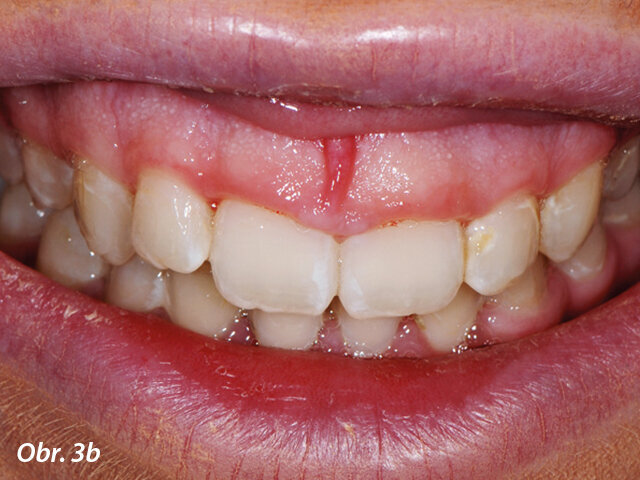

Hyperplazie gingivy před ošetřením.

Gingivoplastika týden po operaci.